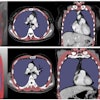

To evaluate the use of automated CT-based measures of body composition for identification of metabolic syndrome in adults without symptoms, the researchers retrospectively applied International Diabetes Federation criteria for diagnosing metabolic syndrome to 7,785 adults who had received low-dose, unenhanced abdominal CT for routine colorectal cancer screening between 2004 and 2016 at their institution.

Of these patients, 738 (9.5%) met the criteria for metabolic syndrome, and subsequent major cardiovascular events occurred significantly more frequently in this group of patients (p < 0.001). Next, the CT exams of all 7,785 patients were analyzed by image-processing and deep-learning algorithms previously developed at the University of Wisconsin for quantifying muscle, visceral and subcutaneous fat, liver fat, and abdominal calcification.

The researchers found a significant difference for all abdominal CT-based biomarker measures between patients with metabolic syndrome and those who did not have the syndrome (p < 0.001).